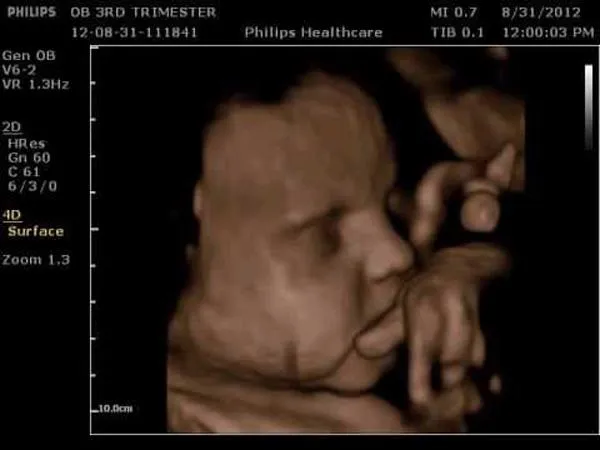

Mang thai lần thứ 3 này được vài tháng chị có đi siêu âm và hỏi bác sĩ về giới tính em bé thì được tiết lộ là bé trai. Sau đó, chị vẫn đi siêu âm định kỳ hàng tháng nhưng mặc định là đang bầu bé trai, thậm chí trước khi sinh vì dáng bụng nhọn nên cũng mặc định là con trai nên vợ chồng chị cũng không nghĩ gì thêm.

Bên cạnh đó, vì đã từng sinh nở 2 lần nên biết đứa con thứ ba là con trai nên khi mua sắm đồ đạc gia đình chị chỉ chọn toàn đồ cho bé trai. Tuy nhiên, ở lần sinh con thứ 3 này khiến chị và gia đình không thể nào quên. Bác sĩ bế em bé ra và thông báo “Con gái nha , 3,2kg"  khiến chị Hương ngơ ngác "hay bị trao nhầm con" vì trước đó khi đi siêu âm đều được báo là sẽ sinh con trai. Cả gia đình chị Hương ai cũng bất ngờ vì trước đó đã thông báo với họ hàng hai bên về giới tính của em bé.

Cả thai kì siêu âm con trai nhưng chào đời lại là con gái.